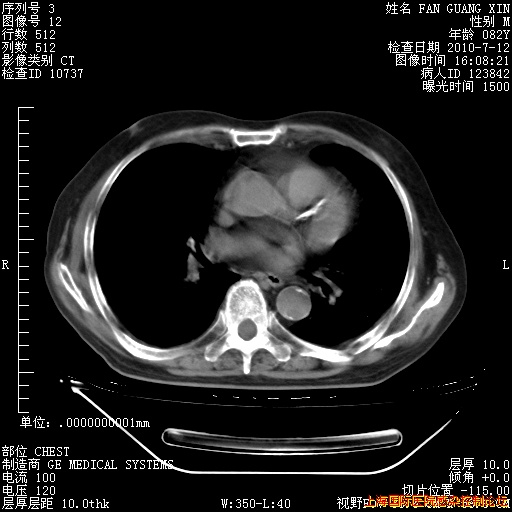

6月12日纵膈窗

今天复查CT

今天CT

整整相隔30天的肺部CT好像有所好转啊。甲强龙减量第3天,需要观察体温。